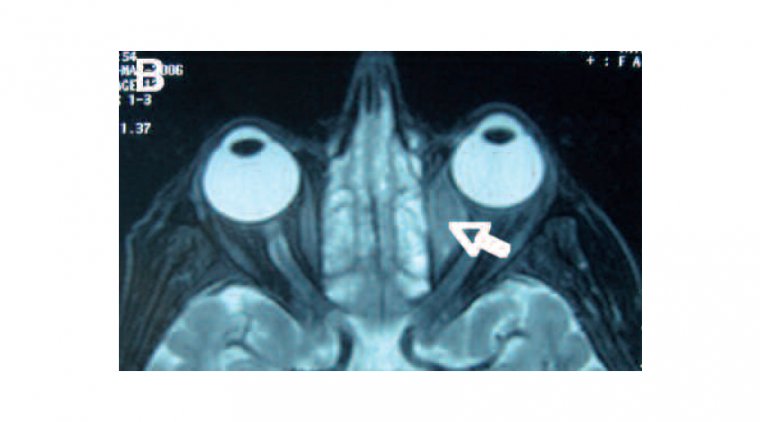

Отёк или выпячивание глаза: один из наиболее частых признаков — заметный отёк или экзофтальм, которые могут сопровождаться болью или чувством давления в области глаза.

Изменения зрения: у пациентов с орбитальной лимфомой могли наблюдаться затуманивание зрения, диплопия (двоение) или его потеря.